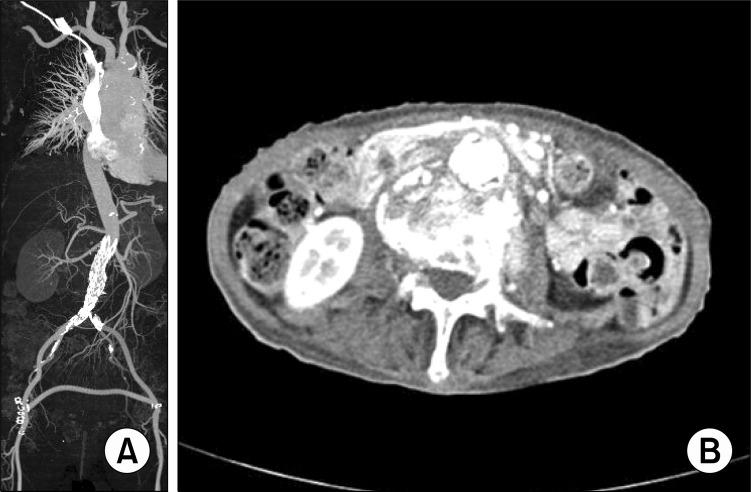

The generally accepted treatment for infected aortic aneurysms involves open surgical resection and debridement, with in situ or extra-anatomical bypass. Occasionally, endovascular management can be substituted for the standard operation dependent on the patient's condition. We report the case of an 81-year-old female with a ruptured infected aortic aneurysm and sepsis, successfully treated endovascularly. She had been on oral antibiotics for one year and is doing well 2 years after discharge.

感染性主动脉瘤的公认治疗方法包括开放手术切除和清创,并进行原位或解剖外旁路移植。偶尔,根据患者情况,可采用血管腔内治疗替代标准手术。我们报告一例81岁女性患者,患有破裂性感染性主动脉瘤并伴有脓毒症,成功接受了血管腔内治疗。她已口服抗生素一年,出院两年后情况良好。